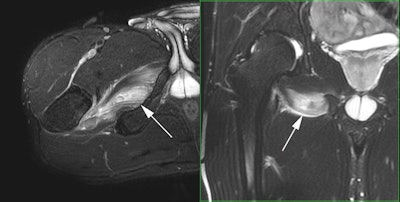

Professional tennis player with acute onset right groin pain during a match. Axial and coronal fat-saturated T2-weighted MR images demonstrate an acute injury of the right obturator externus muscle with a small focal hematoma. All images courtesy of Dr. Ara Kassarjian.